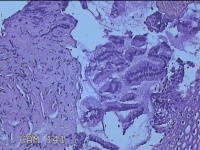

宫颈11点组织

性别

女

年龄

28岁

临床诊断

子宫颈上皮瘤样病变

一般病史

无

标本名称

大体所见

灰白暗红色组织0.7x0.5x0.2cm一块。